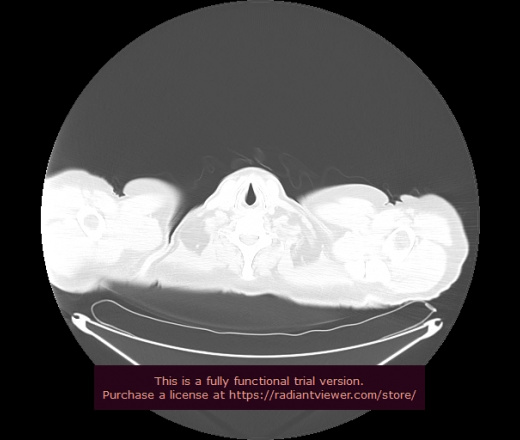

Уважаемые коллеги, если имеется интерес, сможете ли Вы спрогнозировать дальнейшее +-одинаковое течение процесса у 4 данных разных пациентов? Зацепиться где-то можно очень просто, где-то нельзя.